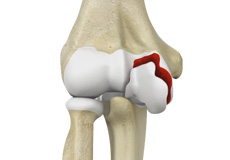

Septic Arthritis

Septic arthritis also called as infectious arthritis, is characterized by joint inflammation due to a bacterial or fungal infection that usually affects the large joints of the body such as knee or hip.